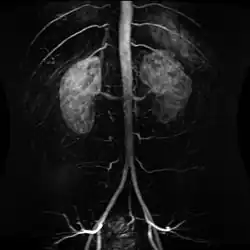

Contrast enhanced MRA of the abdominal aorta demonstrating normal paired arteries. -